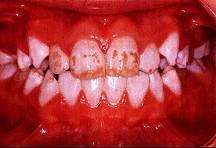

问题 关于氟斑牙的临床表现下列哪项不正确 ( )

选项 A.多见于乳牙和恒牙 B.同一时期萌出的釉质上有黄白相间斑块 C.重者并有釉质缺损 D.对酸蚀的抵抗力强 E.对摩擦的耐受性差

答案 A